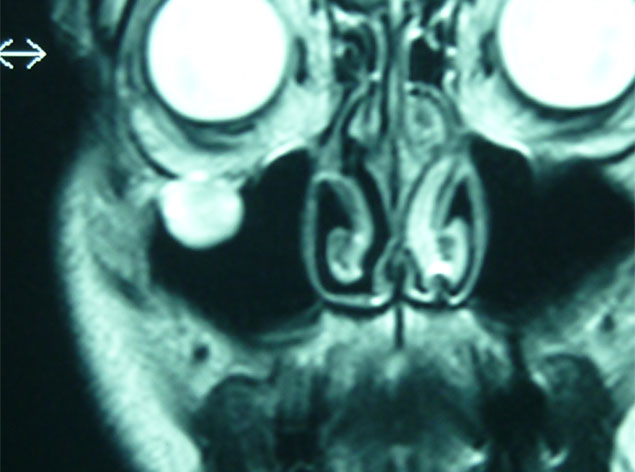

Cuando estos tumores solo afecta a piel se pueden operar bajo anestesia local y sedación, sin embargo cuando afectan a partes óseas la anestesia general es necesaria.